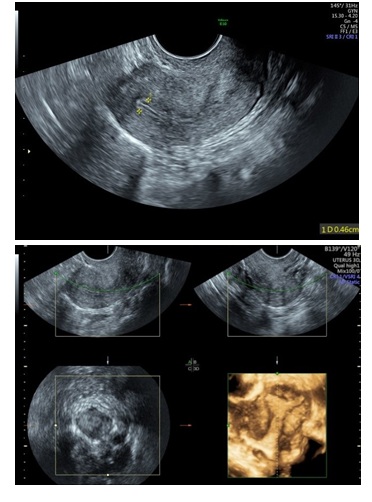

Figure 5: 2D & 3D USG showing Polyp in Uterine Cavity.

Three-Dimensional Ultrasonography (3D USG) in comparison to hysteroscopy is less invasive, cheaper, easily accepted by most patients and does not require much training. In most cases an endometrial polyp can be differentiated from the submucous fibroid based on the imaging characteristics. The polyps are typically round in shape, smooth in outline, and are generally echogenic, compared to the endometrium or are isoechoic to it. The underlying endometrial-myometrial interface is preserved (Figure 5). Moreover the presence of a vascular pedicle has a positive predictive value of up to 81.3%. Fibroids are more inhomogeneous, hypoechoic, and there is a loss of endometrial-myometrial interface. The percentage of the intra cavitary portions of the submucous fibroids i.e., grade of submucous myoma can be assessed on 3D USG by the degree of distortion caused by it (Picture 6).